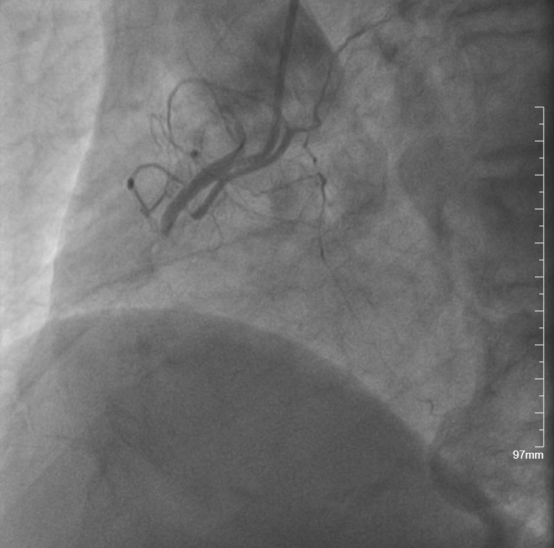

◆冠脉三支严重病变,其中右冠状动脉急性闭塞,为本次发病罪犯血管